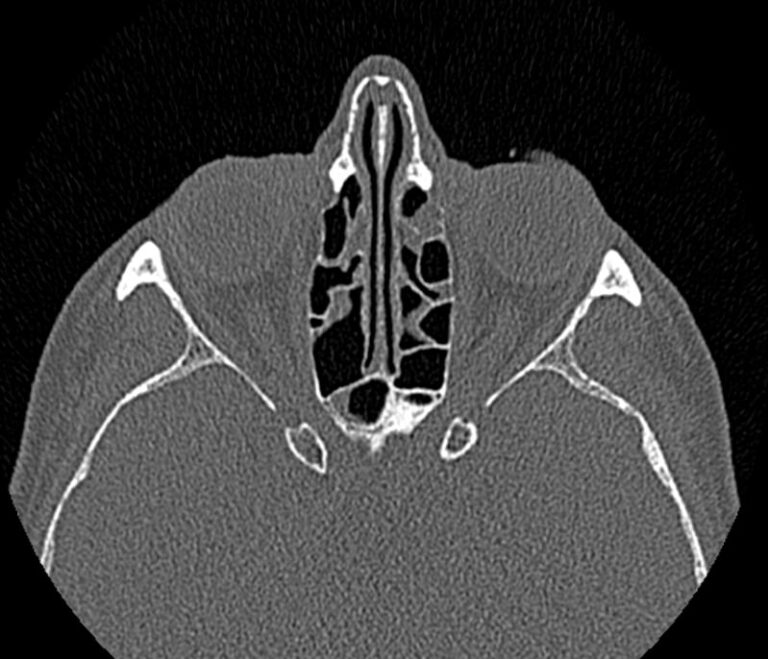

Золотым стандартом в диагностике патологических процессов пазух носа является мультиспиральная компьютерная томография, которая является быстрым безболезненным и неинвазивным (то есть без вмешательства в организм) способом исследования состояния синусов. Метод основан на проникающей способности ионизирующего излучения и получения изображений органов и тканей организма за счет разной степени поглощения ими рентгеновских лучей.

На основе полученных данных цифровые приложения томографов создают трехмерные реконструкции пазух носа, что позволяет оценить пространственное взаимоотношение анатомических структур и помогает в диагностике патологии околоносовых пазух.

Мультиспиральная компьютерная томография дает информацию о состоянии полости носа, носовой перегородки, степени воздушности околоносовых пазух, путей дренирования синусов, состоянии слезных каналов. Сканирование позволяет оценить толщину слизистой, наличие патологического содержимого в просвете пазух (уровня «жидкости»), выявить опухолевые образования. С помощью КТ можно провести точную диагностику травматических повреждений костей лицевого черепа, определить локализацию инородных тел, попавших в полости синусов.

С помощью объемной реконструкции можно перед оперативным вмешательством увидеть особенности анатомии ЛОР-органов, определить точное расположение патологического очага по отношению к окружающим тканям. Компьютерная томография помогает в диагностике аномалий развития придаточных пазух носа, слезоотводящих каналов.